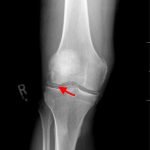

Radiographs of the knee showed multiple radio-dense lines paralleling the articular surface (see red arrows) consistent with calcium pyrophosphate crystal deposition within the joint often seen in calcium pyrophosphate disease (CPPD) also known as pseudogout.

Patients commonly present to the emergency department with non-traumatic joint pain. Arthrocentesis is an important diagnostic tool to evaluate for septic arthritis, gout, or pseudogout. Arthrocentesis can demonstrate crystals or abnormal cell count, gram stain, and culture.[1] In the evaluation of joint pain, plain films are usually obtained to evaluate for fracture, dislocation, effusion, or secondary signs of infection. In this case the classic x-ray supported the diagnosis of CPPD.2 The patient was found to have positively birefringent rhomboid shaped crystals consistent with pseudogout on arthrocentesis. Gram stain and culture were both negative. The patient was discharged with NSAIDs and had significant improvement in symptoms upon follow up with primary care physician in 3 days.